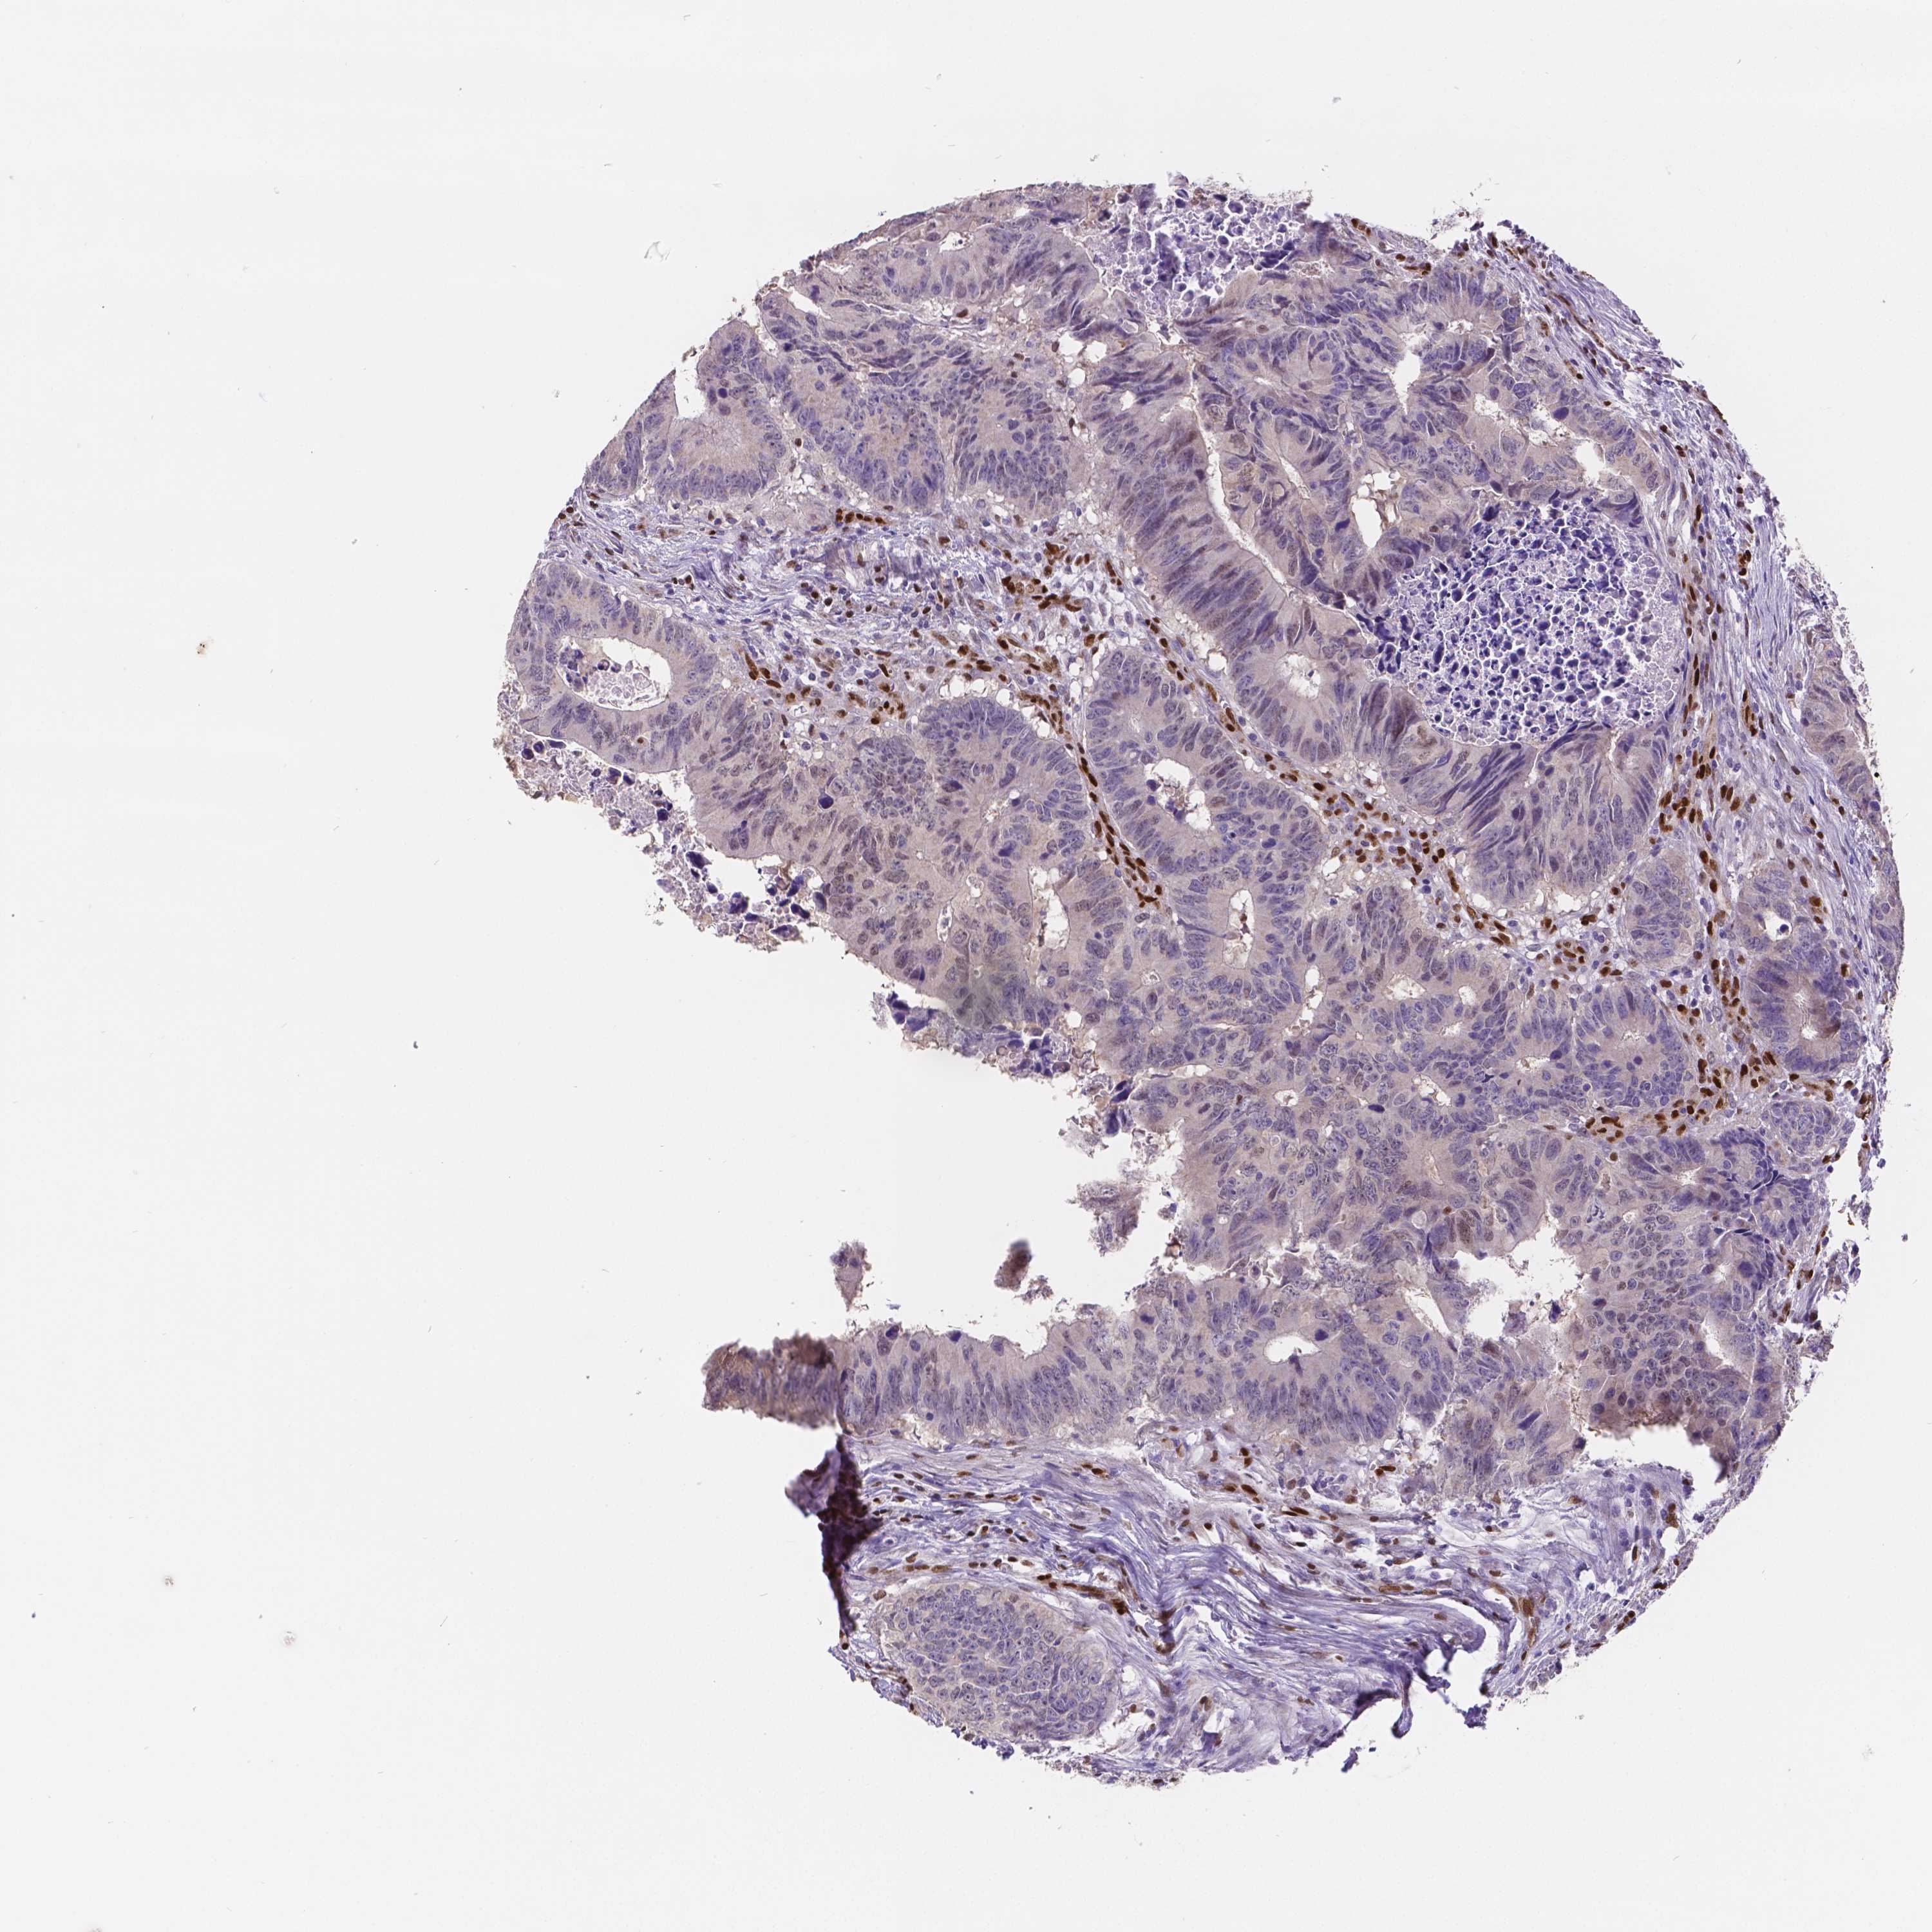

COAD TCGA COAD VALIDATION READ TCGA READ VALIDATION PROTEIN COAD CPTAC PROTEIN EXPRESSION

ANTIBODIES

AND

VALIDATION